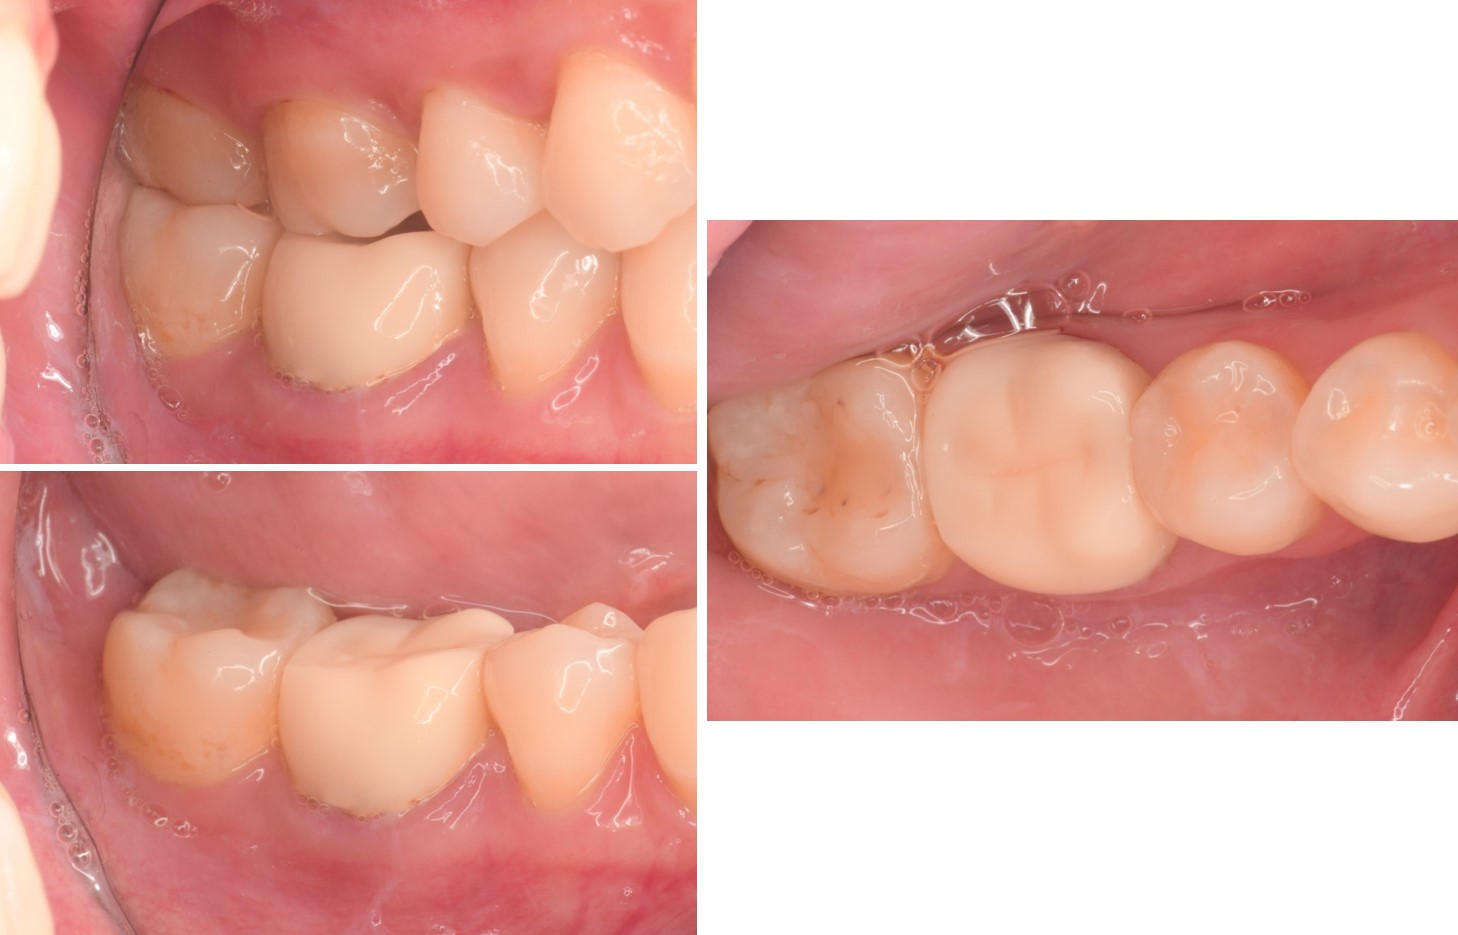

治療前,右下第一大臼齒腫脹

治療後,牙周咬合良好

治療後,密合度良好